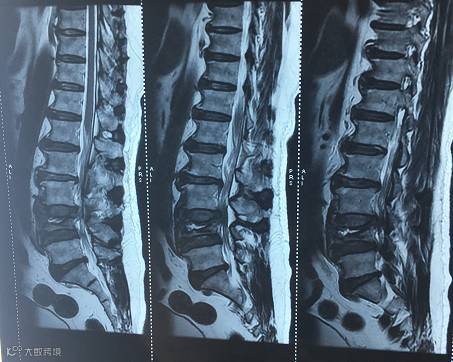

【术前核磁共振】

8月25日,石某来到我院骨科,经详细的检查发现,石某的腰4椎体出现爆裂性骨折与腰椎退行性变,是少见的胸腰椎陈旧性骨折不愈合导致的腰椎问题。